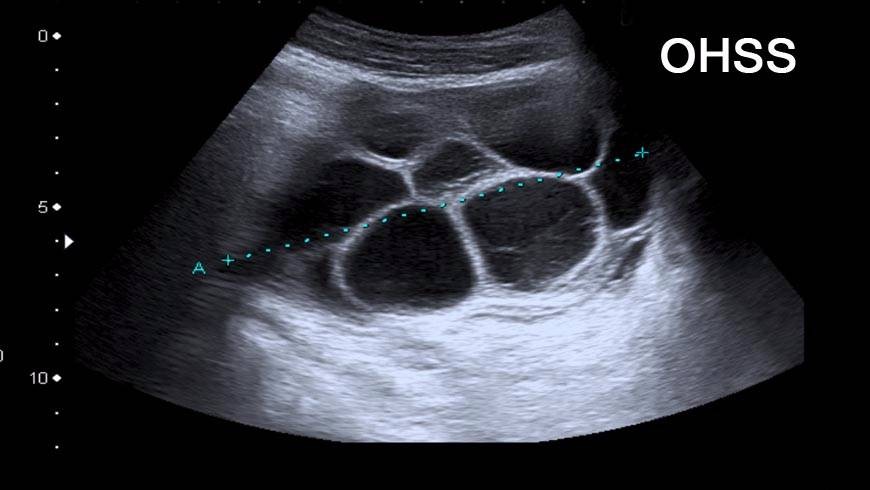

ПовечеСиндром на яйчниковата хиперстимулация

Публикувано на: 23.02.2008 Синдромът на яйчниковата хиперстимулация (Ovarian hyperstimulation syndrome - OHSS) е свръхреакция к...